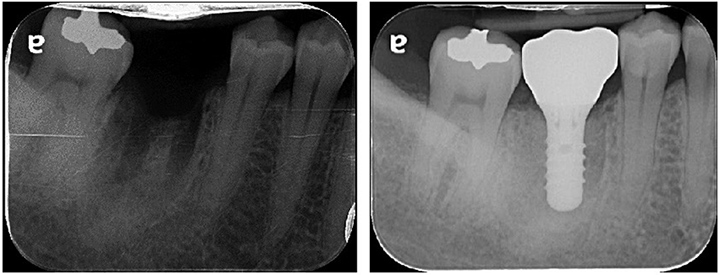

人工植牙治療簡易流程介紹:(如牙科X光所示以植牙重建右下第一大臼齒缺牙區)

結合牙科3D電腦斷層(圖一)以及模型匯入軟體,在植牙手術前先電腦輔助設計補綴物重建位置(圖二),並確認手術位置之骨頭條件,包含寬度、高度以及周圍相關重要構造(神經血管、上顎竇),並藉此規劃在手術前與病患充分討論說明治療計畫,確認後列印製作出數位植牙導板(圖三),於植牙手術時運用此導板可精準、快速以及安全的把植體置放於術前規劃之理想位置並完成後續補綴物製作(圖四)。